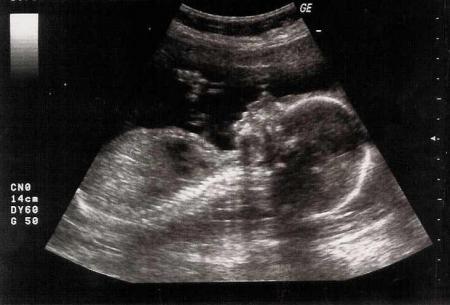

Là il n'est pas encore né, c'est l'échographie du 5ème mois : on distingue bien son petit profile !